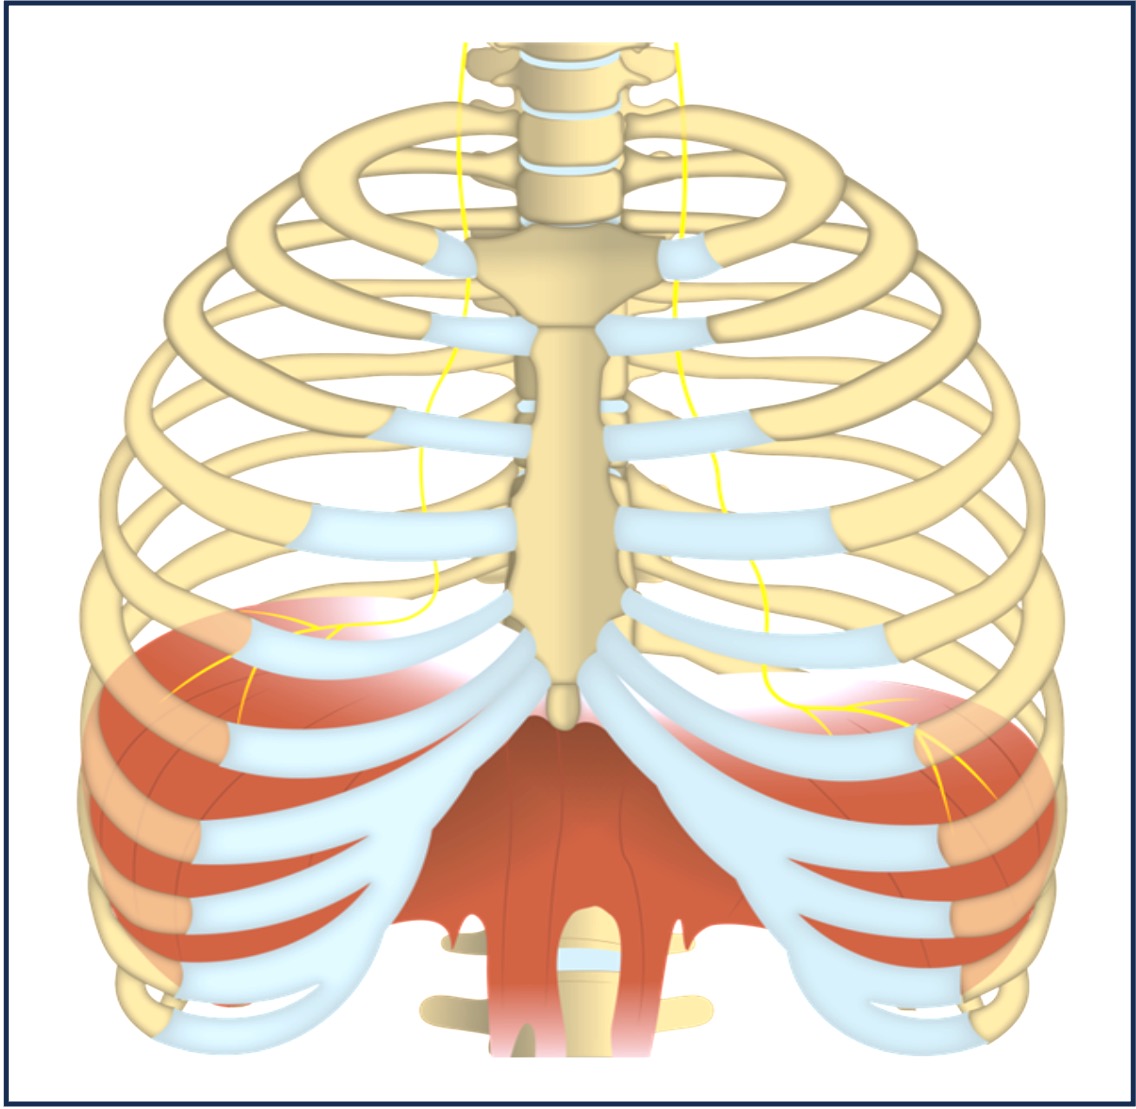

Diaphragm

Inspiration

The diaphragm muscles contract, causing the diaphragm to flatten and increase the volume of the thoracic cavity

External intercostals contract, pulling ribs upwards and outwards (expanding chest)

As the volume of the thoracic cavity increases, the pressure within the lungs decreases below atmospheric pressure and air moves into the lungs

Expiration

The diaphragm muscles relax, causing the diaphragm to curve upwards and reduce the volume of the thoracic cavity

Abdominal muscles contract and push the diaphragm upwards during forced exhalation